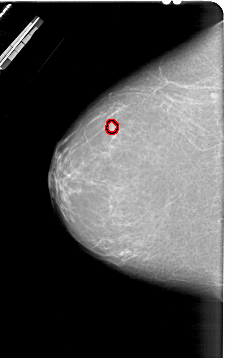

A_1830_1.LEFT_MLO

LEFT_MLO LINES 6871 PIXELS_PER_LINE 3556 BITS_PER_PIXEL 12 RESOLUTION 43.5 OVERLAY

FILE: A_1830_1.LEFT_MLO.OVERLAY

TOTAL_ABNORMALITIES 1

ABNORMALITY 1

LESION_TYPE MASS SHAPE OVAL MARGINS ILL_DEFINED

ASSESSMENT 4

SUBTLETY 2

PATHOLOGY BENIGN

TOTAL_OUTLINES 1

BOUNDARY